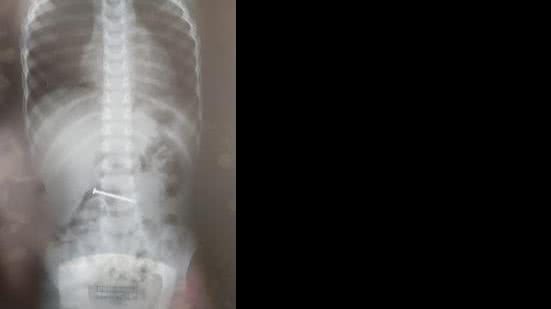

Na unidade de saúde, a equipe médica submeteu a criança a exames de radiografia. O resultado apontou a presença de um prego dentro da barriga da criança.

Os pais foram orientados a observar, até que o objeto seja expelido pelo corpo por meio das fezes. Caso contrário, a criança deverá ser submetida a um procedimento cirúrgico para a retirada do prego.